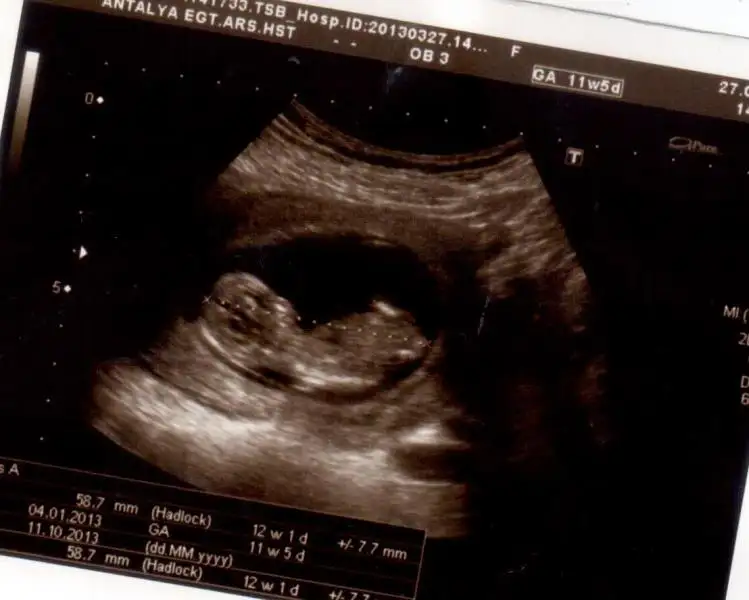

buda benim ilk çekilen fotolardan nub çok büyük erkeğe dönecek nub demişti orkdm ve erkek denildi bence senin bebeğinde erkek bu kadar büyük nub olmuyor çünkü:))))